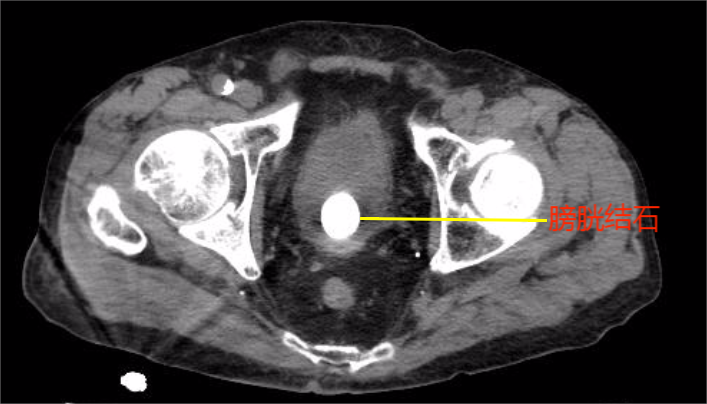

老人今年已88岁高龄,多年来饱受尿频、排尿困难折磨,生活质量受到严重影响。近日,因排尿困难加重遂在家人陪同下来院就诊,经过检查发现老人为前列腺增生及膀胱结石。将老人收治住院后,泌尿外科主任曹东升主任医师团队高度重视,在详细了解病史及查看影像资料后,发现患者高龄并伴有冠状动脉粥样硬化性心脏病、中重度混合性通气功能障碍、慢性支气管炎伴肺气肿,有冠脉支架置入术等病史,且老人已近九旬高龄,是临床上通常被列为的手术禁忌者,如采取保守治疗,前列腺增生引起的排尿功能障碍得不到根本性解决,不仅会带来泌尿系统感染、结石,肾功能损害等严重后果,更对老人的生活质量及心理健康产生严重影响。

考虑到老人强烈的个人意愿,经过麻醉科、心血管内科、呼吸与危重症医学科等多学科会诊,并取得患者家属认可后,最终决定采用微创手术。经过精心的术前准备,在手术室的密切配合下,曹东升主任带领的泌尿外科团队,利用高清腹腔镜、肾镜、高功率钬激光、前列腺等离子电切仪等一大批先进设备,顺利为患者实施了“经尿道输尿管镜下钬激光联合碎石+前列腺等离子电切术”,手术历时1小时30分。